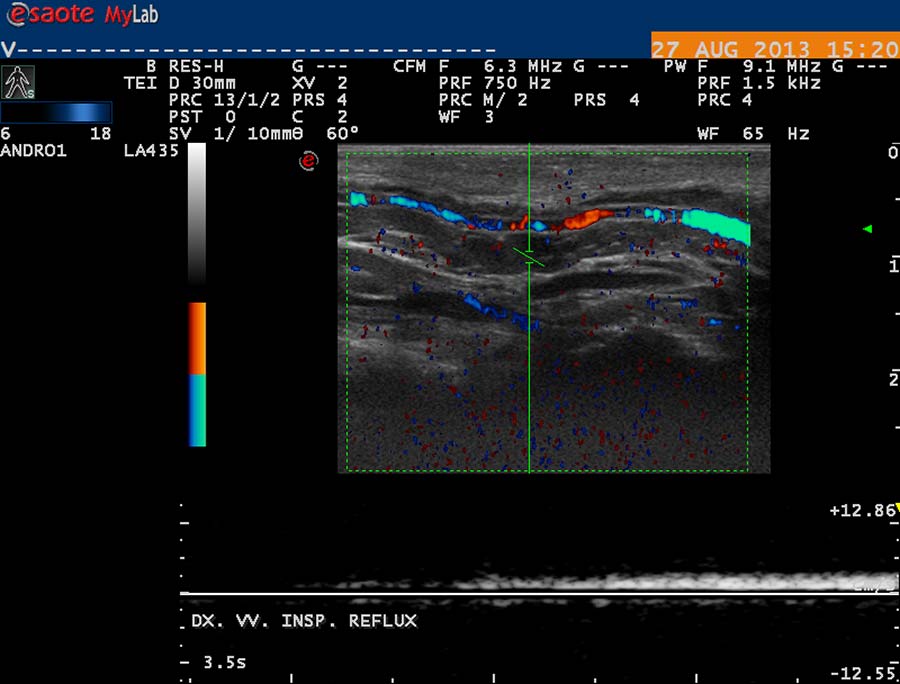

USG diagnostika vyžaduje odpovídající vybavení (obr. 12), zkušenosti a dostatek času. Vyšetření USG provádíme po termografickém vyšetření, na lůžku vyhřívaném na 30 st. Celsia, ultrasonografický gel zahříváme ve vodní lázni na teplotu 35 stupňů. Chladová kontrakce musculus cremaster vede k falešně negativním nálezům. Základní projekcí je koronární sken varlete (obr. 14) následovaný volumometrií ve dvou rovinách (obr. 15). Již na těchto skenech varlete je patrné rozšíření intratestikulárních cév, lépe je však viditelné při harmonickém („tissue enhancement imaging – TEI“) zobrazení (obr. 16, 17), a při barevném Dopplerovském zobrazení (Power Doppler) s TEI (obr. 18) s měřením šíře stěny a lumen žíly. Objemné dilatované žíly pampiniformního plexu jsou velmi dobře patrné na kolorizovaném TEI zobrazení (obr. 19), kde je možné zachytit pohyb venózní krve v souvislosti s dechem, intraabdominálním (IAP) a intrathorakálním tlakem. Informaci o atrofizaci tkáně získáme ze záznamu deformace kontury tunica albuginea podložkou, kterou je měkká buničina vložená pod skrotum (obr. 20, obr. 21 s volumometrií). Triplexní Dopplerovský záznam umožní hodnotit délku žilního refluxu a rychlost proudu refluktující krve v inspiriu, reflux při zvýšení intraabdominálního tlaku (obr. 22,23). Duplexní Dopplerovský záznam při harmonickém zobrazení s kolorizací zachycuje senzitivně změnu rychlosti proudění při refluxu v inspiriu s navazujícím zvýšením rychlosti při IAP (obr 25). Významná je možnost zachycení refluxu při klidném dýchání (respirační reflux, obr. 26).

obr. 26